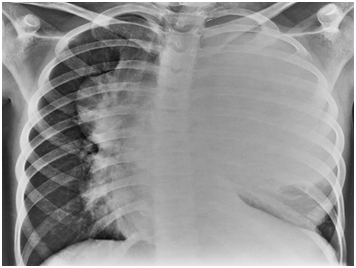

Figure 1 Large soft tissue density mass in left hemi-thorax extending contra laterally with mild right sided mediastinal shift.